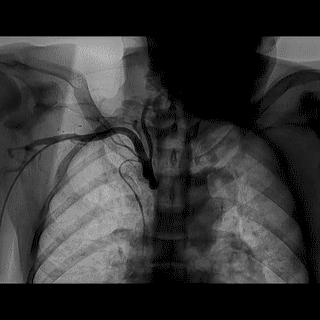

第一步:在主动脉窦部行非选择性造影(包括升主动脉造影),寻找异常开口位置;

第二步:更换特殊的造影导管,如AL1.0,AL1.5或其它。

➢ CASE 1

➢ CASE 2

右冠起源异常,开口于左冠窦